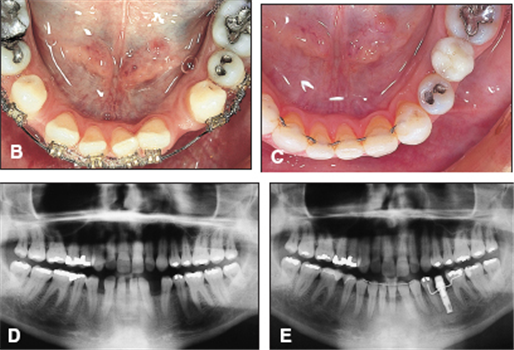

노년이 되면서 치아를 한 두 개씩 상실하게 됩니다.

이를 장시간 방치하면, 인접치와 대합치가 이동하게 되어 맞물림이 나빠집니다.

노년이 되면서 치주상태가 안 좋아질 수 있습니다.

이는 치아를 지지하는 치조골이 내려가는 것으로

치아의 지지기반이 약해지기 때문에 치아가 흔들리는 주요인이 됩니다.

이 시기의 교정치료로 약해진 치주상태가 원상태로 회복되기는 어렵습니다.

다만 교정치료를 통해서 치아를 관리하게 편한 상태로 유지시켜

치주상태가 더 나빠지는 것을 막아 주는 것입니다.